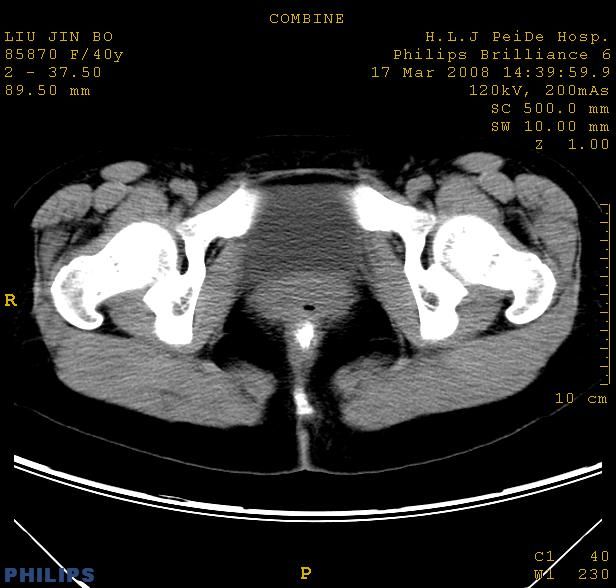

以下是引用qiuleiyu在2008-4-27 12:36:00的发言:[br]支持;右侧腰大肌后方神经源性肿瘤可能大,神经节细胞瘤?

以下是引用形影不离在2008-4-27 14:11:00的发言:[br]1.考虑右侧腰大肌脓肿。[br]2.左侧附件区炎症。[br]3.子宫增大,建议:进一步检查。